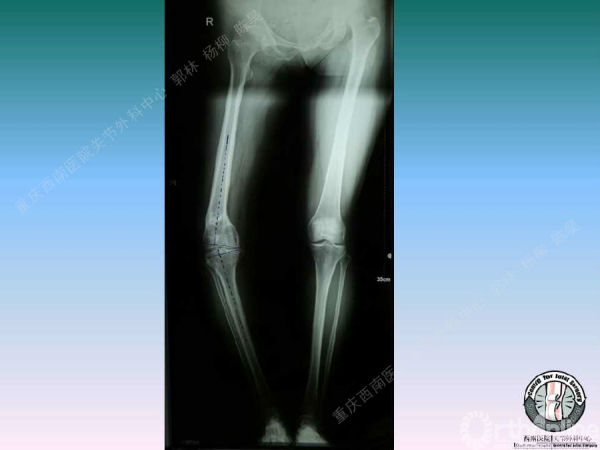

导读:文中,来自重庆西南医院的郭林教授为大家介绍了股骨冠状位关节外畸形的TKA的相关知识,并详细阐述了关节外畸形的概念、诊断、关节内滑移截骨技术等相关内容。

滑移截骨纠正关节外畸形